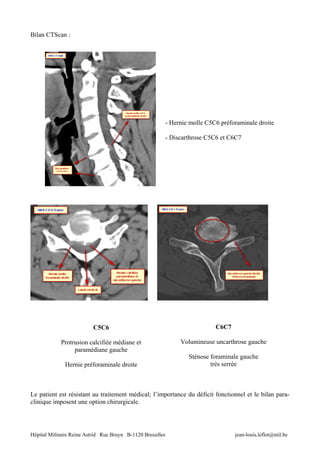

Bilan CTScan :

- Hernie molle C5C6 préforaminale droite

- Discarthrose C5C6 et C6C7

C5C6                                                C6C7

Protrusion calcifiée médiane et                      Volumineuse uncarthrose gauche

paramédiane gauche

Sténose foraminale gauche

Hernie préforaminale droite                                   très serrée

Le patient est résistant au traitement médical; l’importance du déficit fonctionnel et le bilan para-

clinique imposent une option chirurgicale.